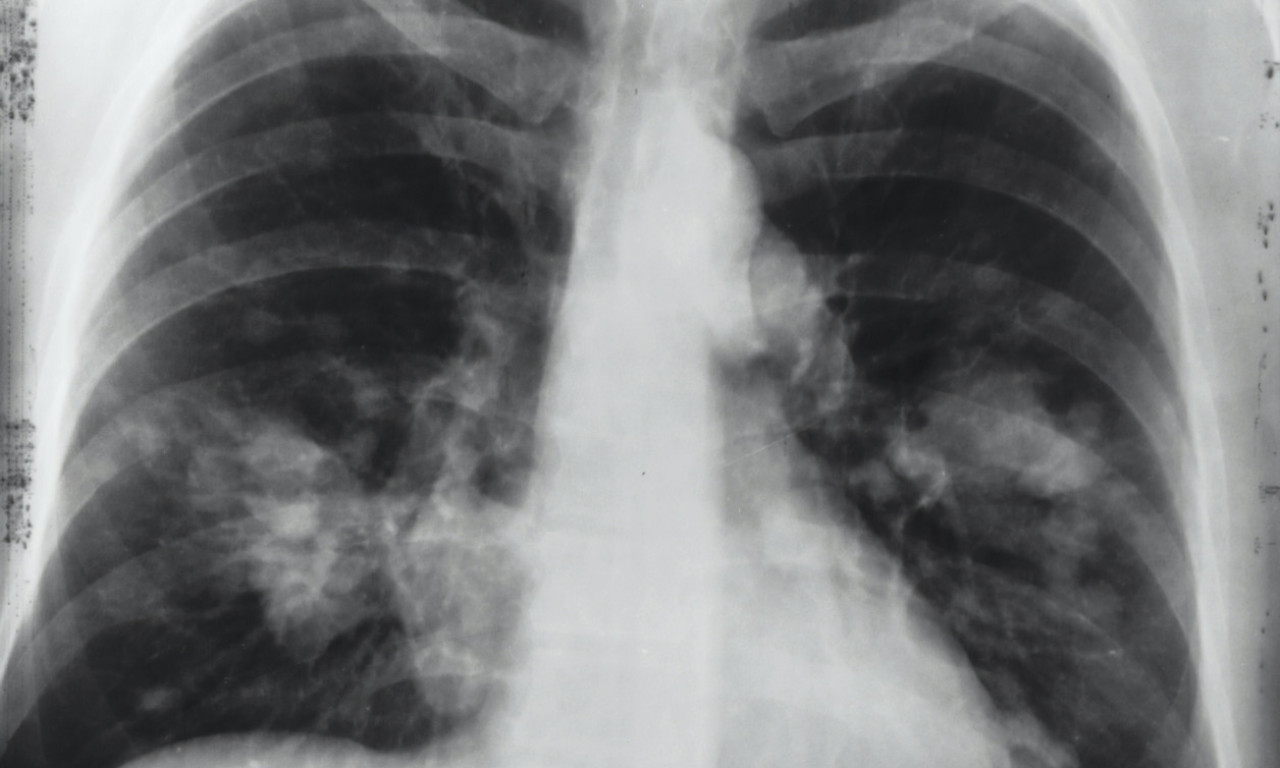

rak pluća

VEŠTAČKA INTELIGENCIJA OTKRIVA RAK PLUĆA MESEC DANA UNAPRED! Potrebno je uraditi osnovne medicinske analize

Na svaka dva sata u Srbiji jedna osoba premine od KARCINOMA PLUĆA! Od jeseni počinje "borba" u SRBIJI, a evo i kako

Svetski dan borbe protiv raka pluća obeležava se svake godine 1. avgusta.

Rak pluća je vodeći uzrok smrti od raka u svetu, a godišnje ima 1,8 miliona smrtnih slučajeva od kancera pluća

ALARMANTNI PODACI U SRBIJI! Od RAKA PLUĆA oboli 7.000 SRBA godišnje, što nas stavlja na drugo mesto u Evropi

CRNA STATISTIKA: 70% obolelih RAK PLUĆA otkrije tek kad su ŠANSE ZA IZLEČENJE MINIMALNE, ovo je NAJVEĆI PROBLEM

Doktor je objasnio koje metode lečenja postoje u Srbiji i na koji način se određuje da li će pacijent biti podvrgnut inovativnom lečenju

Srbija drži PRVO MESTO u Evropi po smrtnosti od KARCINOMA PLUĆA - zašto je to tako?

Ukoliko se otkrije na vreme, ova opaka bolest je izlečiva